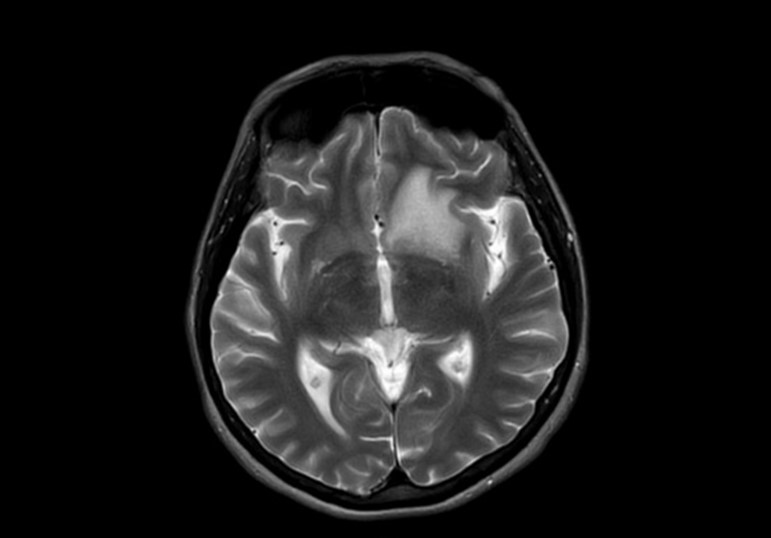

Result of MRI was at T1WI hypointense lesion as seen on (Figure 4), at fluid sensitive sequences T2WI \ FLAIR the lesion is hyperintense as shown in (Figure 5), after GAD enhancement there's irregular ring enhancement of the lesion (Figure 6). Followed by vasogenic edema that is visible in flair sequence at the medial aspect of base of frontal lobe that also affects the head of caudate nucleus. No diffusion restriction was seen in DWI and ADC sequences (Figure7a,7b). In SWI there's no detection of blood products.

Figure 5: Axial T2WI shows hyperintense lesion.